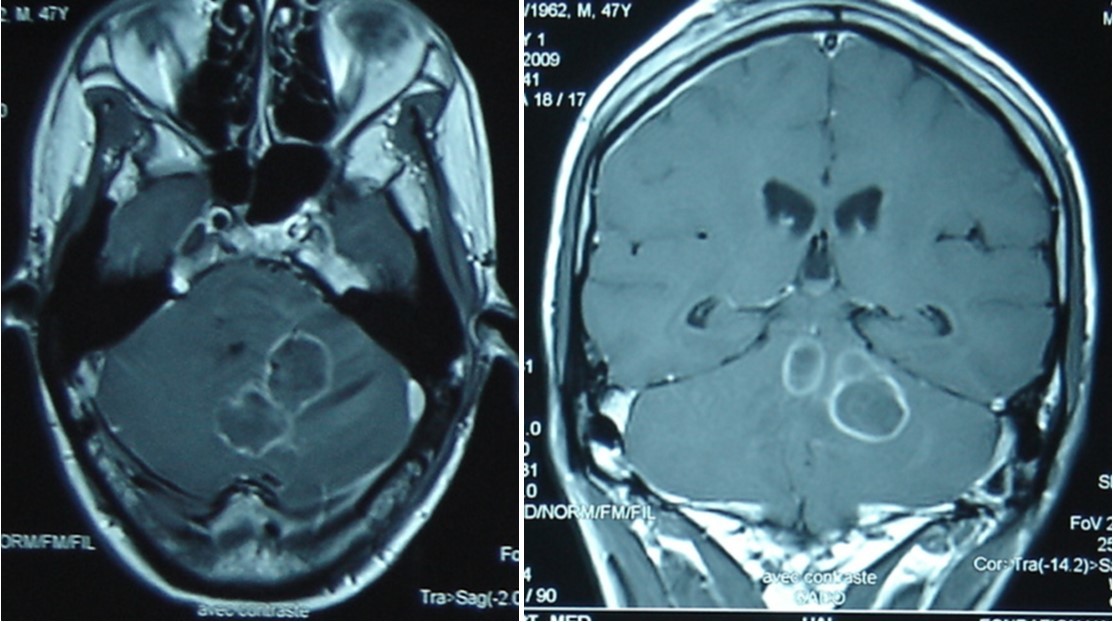

A 47 year old patient with no previous medical history presented with features of raised intracranial pressure, statokinetic cerebellar syndrome as well as left sided hemiparesis. The diagnosis of posterior fossa space occupying lesion was made. Neuroradiologic investigations demonstrated posterior fossa lesions. Magnetic resonance imaging and spectroscopy were in favor of a multiple infective process (Figure 1). Stereotatic biopsy was carried out on the patient and parasitological and histological examinations of the specimen concluded to a filamentous fungal infection of Aspergillus type. Culture and staining techniques categorized the specie as Aspergillus fumigatus (Figure 2).

Figure 1.cerebral MRI axial T1-weighted (A) and coronale (B), showing a multiples well circumscribed posterior fossa lesions